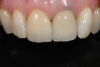

Fig 1. Badly damaged endodontically treated maxillary anterior tooth.

Figure 1

Fig 10. A 24-year follow-up radiograph of an endodontically treated tooth, with a cast post-and-core and adequate tooth structure remaining. The patient had a low smile line and thick phenotype.

Figure 10

Fig 11. Restoration at 24-year follow-up.

Figure 11